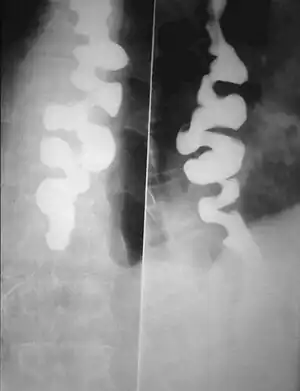

| A barium swallow showing a corkscrew appearance due to distal esophageal spasm | |

Several radiographic findings are suggestive of DES, such as a "corkscrew esophagus" or "rosary bead esophagus" appearance on barium swallow x-ray, although these findings are not unique to DES.[4]